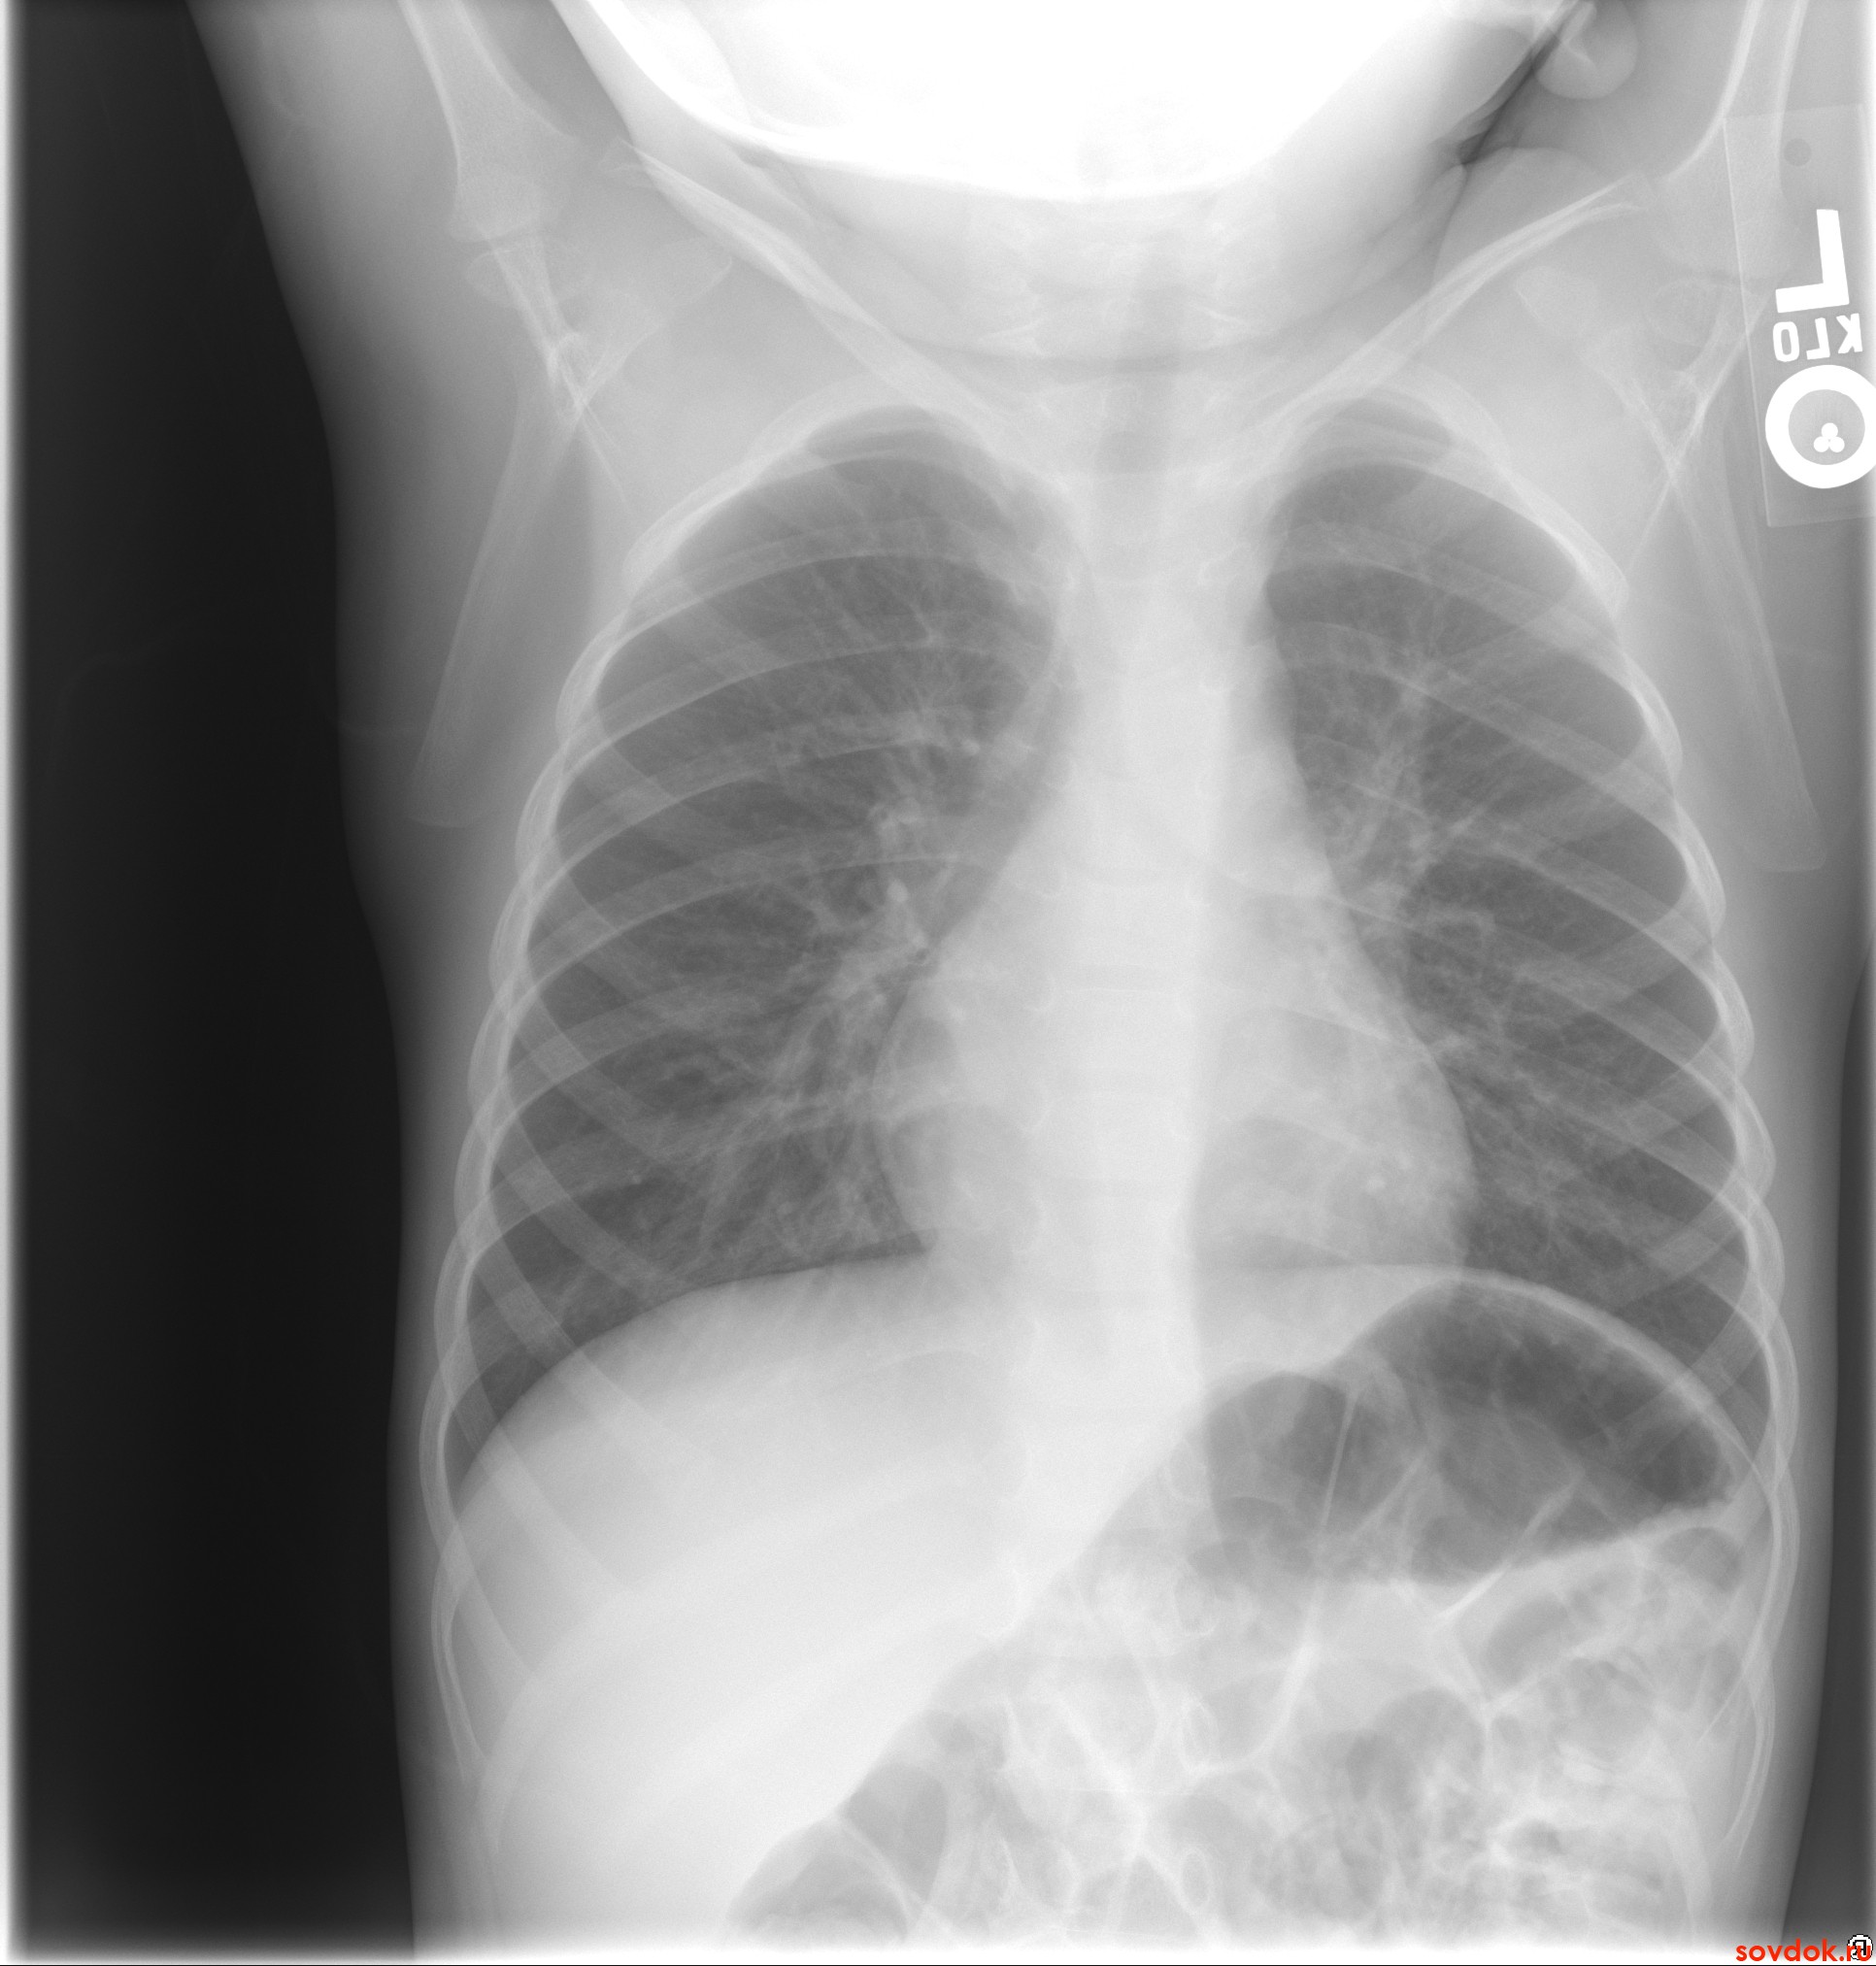

Рентгенологическое исследование

На рентгенограмме печень выглядит как однородная тень, похожая на треугольник. Верхняя граница печени совпадает с диафрагмой, а нижняя граница четко видна рядом с другими органами брюшной полости. Рентгенологическое исследование помогает определить размеры и структуру печени.